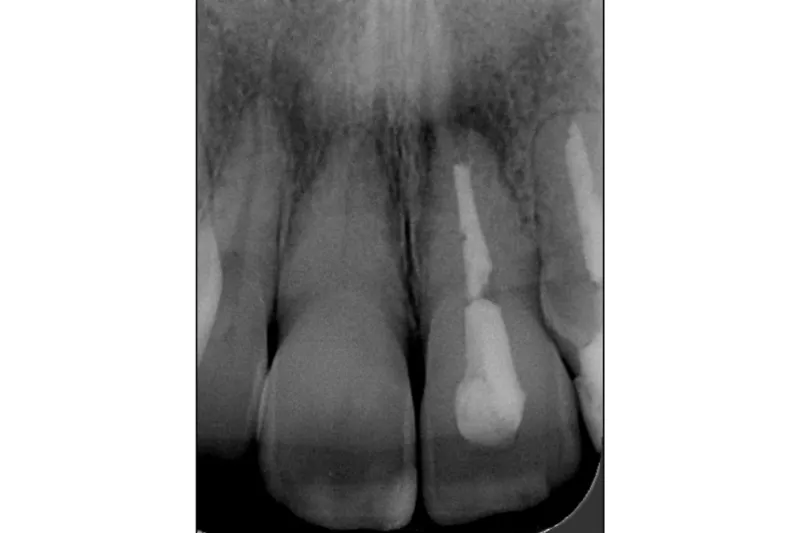

En insufficient rodfyldning revideres, hvis der er infektion i rodkanalsystemet, eller man i forbindelse med koronal restaurering er nødt til at blotlægge rodfyldningen. Kan man undgå at blotte rodfyldningen til det orale miljø, er der minimal risiko for sekundær infektion, og der kan umiddelbart laves en koronal restaurering (Fig.).

Ved diagnosticeret parodontitis apicalis er valgmulighederne revision, endodontisk kirurgi eller ekstraktion (Fig.).

Hvis sygdommen skyldes infektion i rodkanalsystemet, og det er teknisk muligt at eliminere bakterierne, vælges revision. Hvis det ikke er teknisk muligt, eller hvis årsagen til sygdom vurderes at sidde uden for kanalsystemet, vælges apikal kirurgi eller ekstraktion.